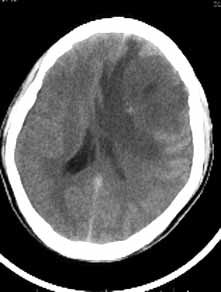

男性,36岁,头痛数年,近期伴有视蒙。

ct诊断:左额颞部脑膜瘤。